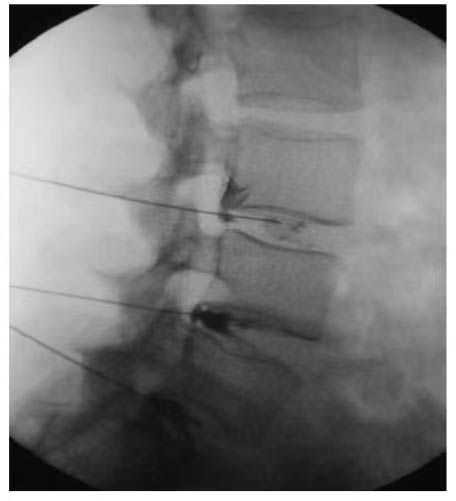

CT-Guided Spinal Injection: Precision Healing, Renewed Hope

Our expert team has pioneered CT-guided intraspinal injection technology, specifically designed for stem cell therapy in spinal cord injury treatment. During the procedure, real-time CT imaging generates dynamic 3D visuals of the spine, allowing surgeons to rotate and analyze fracture locations in multidimensional space. The needle is carefully advanced through a healthy anatomical pathway, avoiding bony obstructions. As the surgeon guides the needle toward the spinal cord, the system continuously updates imaging to verify trajectory angles and spatial relationships between the spinal cord and vertebrae, ensuring absolute precision and safety. This technique is often combined with lumbar punctures or intravenous stem cell therapies for enhanced efficacy.

Advantages of CT-Guided Spinal Injection:

1.Minimally Invasive & Safe

No major incisions required. Performed under local anesthesia with minimal trauma, blood loss, and post-procedural pain, enabling rapid recovery.

2. Submillimeter Precision

CT guidance allows real-time measurement and targeting of injury sites with unparalleled accuracy.

CT-guided spinal injection offers a groundbreaking, safe, and effective solution for spinal cord injury patients, significantly improving clinical outcomes and quality of life. If you or a loved one is battling spinal cord injury, consult our specialized medical team today. Together, we’ll craft a personalized treatment plan to reignite hope and empower your journey toward renewed independence.